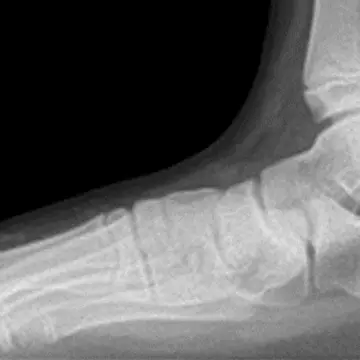

アキレス腱が柔軟だと、足底のアーチがくずれない。

アキレス腱が硬いと、足底を押しつぶし、偏平足に。